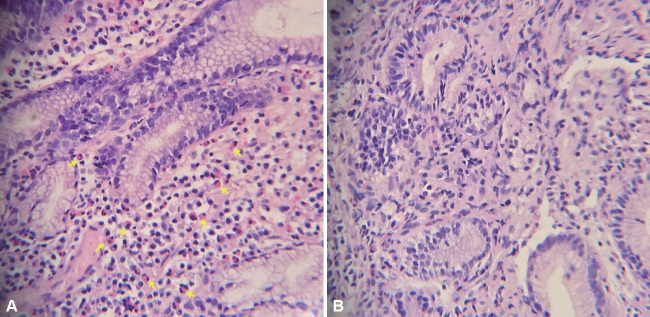

嗜酸性胃炎是一种相对罕见的以嗜酸性胃壁浸润为特征的疾病,病程缓慢,可复发也可缓解。在此,我们描述一个25岁的男子慢性嗜酸性胃炎并发胃出口梗阻的情况。患者自青春期起有持续性胃肠道症状,就诊前2个月出现严重消化不良和呕吐。胃镜检查和活检证实嗜酸性胃炎。类固醇治疗后症状有所改善,但粘膜病变并未完全消除。这个病例显示嗜酸性胃炎可以有一个慢性过程,持续的粘膜病变,尽管症状改善。早期诊断和适当治疗嗜酸性胃炎对预防慢性胃粘膜改变具有重要意义。

Eosinophilic gastritis, a relatively rare condition characterized by eosinophilic infiltration of the gastrointestinal wall, has a chronic course involving relapses and remissions. Herein, we describe the case of a 25-year-old man with chronic eosinophilic gastritis complicated by gastric outlet obstruction. The patient had a history of persistent gastrointestinal symptoms since adolescence and had developed severe dyspepsia and vomiting two months before presentation. Eosinophilic gastritis was confirmed using endoscopy and biopsy. The symptoms improved after steroid treatment, although the mucosal lesions did not completely resolve. This case shows that eosinophilic gastritis can have a chronic course with persistent mucosal lesions, despite symptomatic improvement. Early diagnosis and appropriate treatment of eosinophilic gastritis are important for preventing chronic gastric mucosal changes.